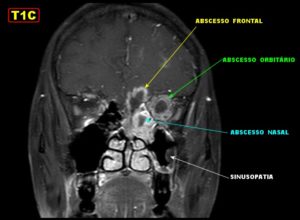

- Инфицирование полости глазницы. Это осложнение чаще всего развивается на фоне сфеноидита с вовлечением решетчатого лабиринта. Поскольку последняя анатомическая структура непосредственно контактирует с полостью глазницы, микробная флора очень легко проникает в эту полость. При этом могут формироваться ретробульбарные (расположенные за глазом) абсцессы, флегмоны. Эти скопления гноя в дальнейшем оказывают давление на глазное яблоко, приводя к его выпячиванию. При вовлечении в воспалительный процесс мягких тканей кожа вокруг глаз становится отечной, красной. Движения глазными яблоками затруднены, пациент старается держать глаз закрытым.

Единственными методами, которые наверняка могут определить сфеноидит, являются компьютерная томография (КТ) или магнитно-резонансная томография (МРТ) –